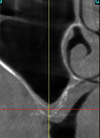

Le cliché 3D pré-opératoire révèle une cloison (ou refend) au sein du sinus maxillaire droit d’une patiente de 67 ans.

Deux fenêtres sont réalisées, l’une en arrière et l’autre en avant du refend, et une membrane d’origine porcine est placée et suturée dans chaque cavité avant le comblement osseux.

Le cliché 3D post-opératoire montre les deux implants vissés de part et d’autre du refend et dans la masse des deux comblements osseux réalisés indépendamment .